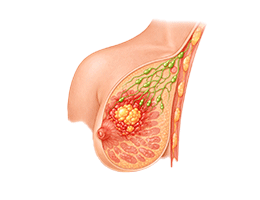

유방암 (Breast Cancer)